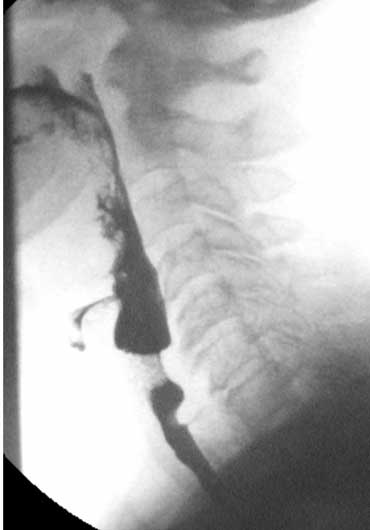

Đây là bộ hình ảnh minh họa một bệnh nhân bị liệt các cơ khít hầu.

Tình trạng này thường đi kèm với giãn không đủ của cơ nhẫn hầu.

Trong ví dụ này, chúng ta có thể thấy bệnh nhân cố gắng bù đắp cho sự mất chức năng co bóp hầu bằng cách cử động quá mức của lưỡi và đầu.

Bệnh nhân này đang trong tình trạng căng thẳng cực độ, vì biết rằng khi bắt đầu thở mà cổ họng chưa trống, sẽ bị hít sặc.

- 1-3. Không thấy co bóp của thành sau hầu họng. Cơ nhẫn hầu không mở đúng cách.

- 4-7. Thuốc cản quang vào thanh quản nhưng không vào khí quản.

- 8-10. Cử động đầu quá mức nhằm đẩy bolus vào thực quản.

Trong một số trường hợp này, phẫu thuật cắt cơ nhẫn hầu là giải pháp duy nhất để tạo điều kiện cho thức ăn đi vào thực quản.